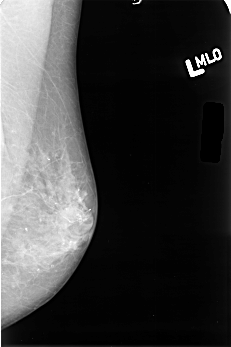

B_3380_1.LEFT_MLO

LEFT_MLO LINES 4504 PIXELS_PER_LINE 2992 BITS_PER_PIXEL 12 RESOLUTION 50 NON_OVERLAY